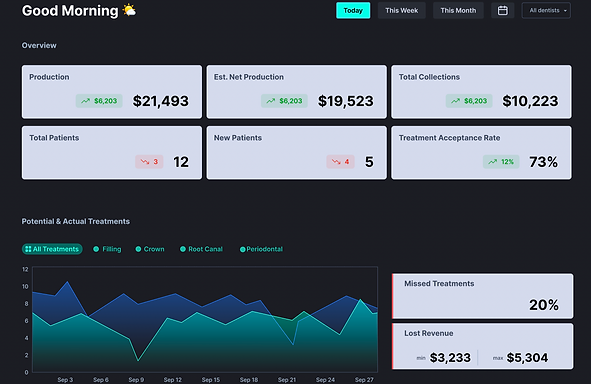

The startup, co-founded by dentist-turned-entrepreneur Dr. Hamed Fesharaki, Yasaman Nemat, PhD, and Shifeng Chen, has just cleared FDA approval for its first AI-driven product, Adravision Perio, that helps dentists and dental hygienists measure bone levels on dental radiographs during an appointment. For busy dentists, the tool can streamline the identification and prevention of gum disease.

Adravision’s Perio software can play an important role in “diagnosing and planning treatments for periodontal disease,” she added. That is particularly important as periodontal disease (gum disease) affects up to 90% of the population.

“In the United States, cross-sectional studies indicate that approximately 50% of adults currently grapple with some form of gingivitis, the initial stage of gum disease. Left unaddressed, gingivitis can progress to periodontitis, posing risks of tooth loss and discomfort during chewing. Adravision's AI-driven solution can help dentists and hygienists more effectively identify signs of periodontal disease and clearly communicate findings with patients in a highly engaging and visual presentation format. Adravision Perio also employs interactive and engaging tool to help dentists and hygienists to better explain problems to their patients which results in more quality and timely care.”

After just two years into operations, Adravision recently secured its initial FDA clearance after displaying that its “automated bone level measurement capabilities [were] akin to a proficient team of dentists,” added Nemat.